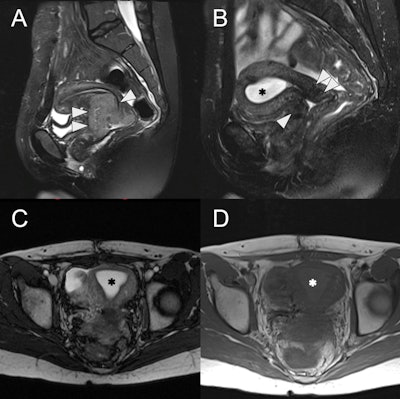

24-year-old female with radiation-induced cervical stenosis. (A) Pretreatment sagittal fat-suppressed T2w MRI of the uterus with a large intermediate to high signal intensity cervical mass (white arrowheads), FIGO stage IIB. (B) Sagittal fat-suppressed T2w MRI postchemoradiation showing marked regression of the tumor (white arrowheads) with reconstitution of the low signal intensity cervical stroma and no measurable residual mass. However, there is new distention of the endometrial cavity (asterisk) with high signal intensity. (C) Axial T2w MRI of the uterus with a distended endometrial cavity (asterisk), suggestive of obstruction. (D) Axial T1w MRI of the uterus shows mild hyperintensity (asterisk) of the endometrial fluid compared to myometrium, suggestive of hematometra

Small volumes of endometrial fluid may be physiologic in premenopausal women. In postmenopausal women, the presence of physiologic fluid is controversial, though often benign if the patient is asymptomatic with normal endometrial thickness, they noted. In postmenopausal women, the differential for hydrometra includes cervical stenosis, cervical or endometrial carcinoma, and infection. “Larger volumes of hydrometra in premenopausal women could relate to congenital obstructions (imperforate hymen, transverse vaginal septum, vaginal or cervical atresia), acquired cervical obstruction due to instrumentation, prior radiation therapy, carcinoma, and pregnancy.”

Cervical stenosis can be congenital, but is most commonly secondary to trauma, infection, malignancy, prior radiation, mass effect from adjacent Nabothian cysts or leiomyomas, or hormone-related changes. Hysteroscopy is the gold standard for diagnosis and treatment, and MRI is used to investigate for underlying causes, the researchers said.